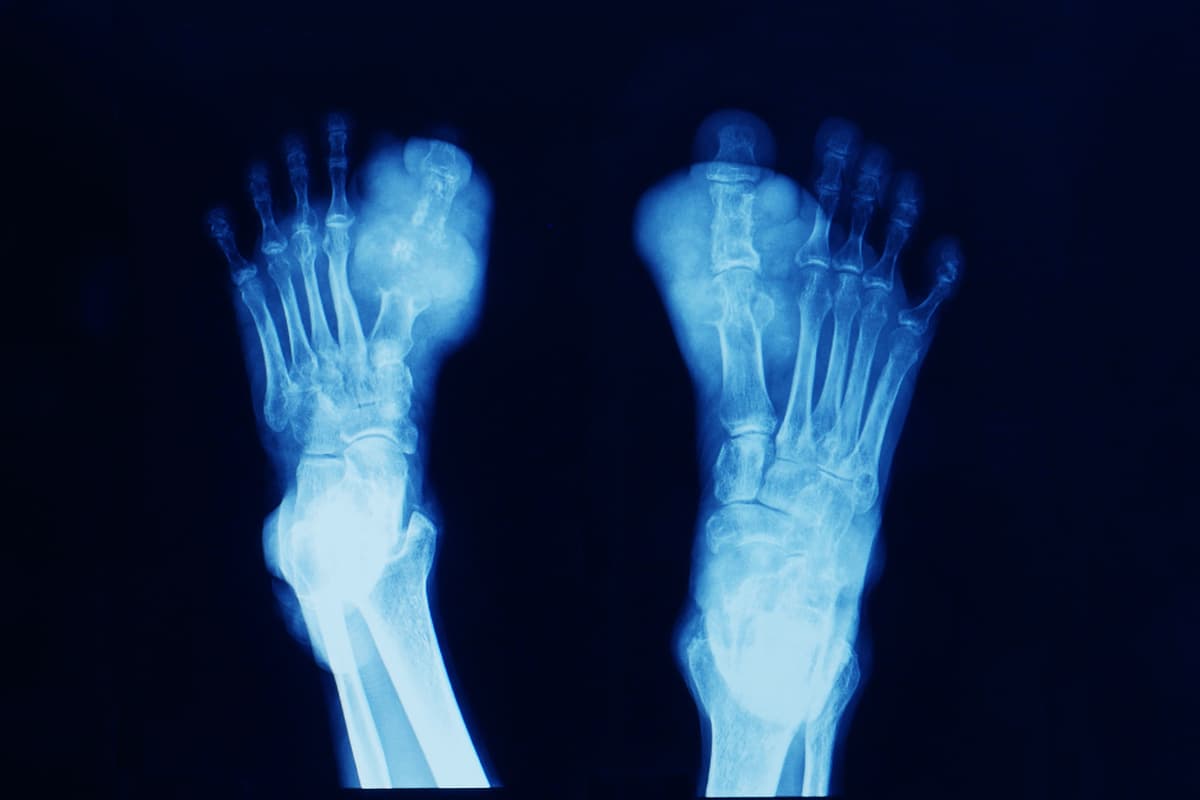

10. Gota

La gota es una enfermedad que en la época antigua era conocida como la "Enfermedad de los Reyes" y una de sus víctimas fue el rey Enrique VII de Inglaterra, pero sigue vigente en nuestros días.

De acuerdo con la BBC, desde 2012 se han vuelto a registrar brotes de esta infección provocada por la acumulación del ácido úrico en las articulaciones.

Inglaterra, Australia y Nueva Zelanda son los países donde la enfermedad es más recurrente, con una cantidad de infectados de entre 10 mil hasta 30 mil pacientes por año en cada nación.